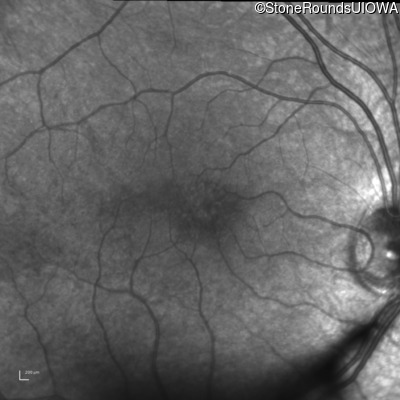

Infrared Fundus Photograph - Left - 20/40 +2

Exemplar